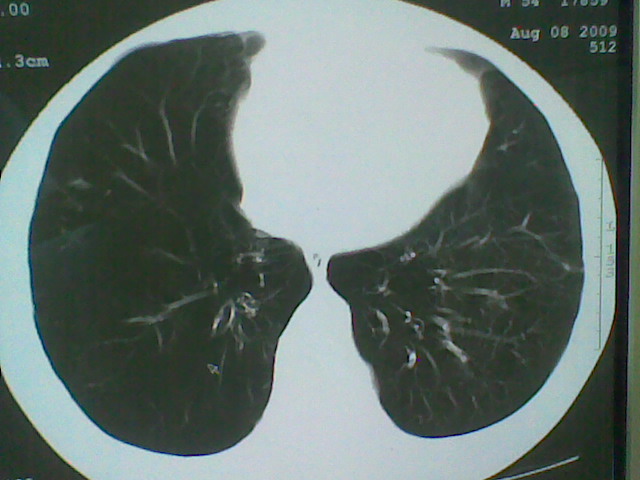

标题: CT21512:支扩伴感染?

患者女。咳嗽数天,咯血半天。

我们报的是支扩伴感染?

支持楼主意见,还有肺气肿

可以诊断为支扩。